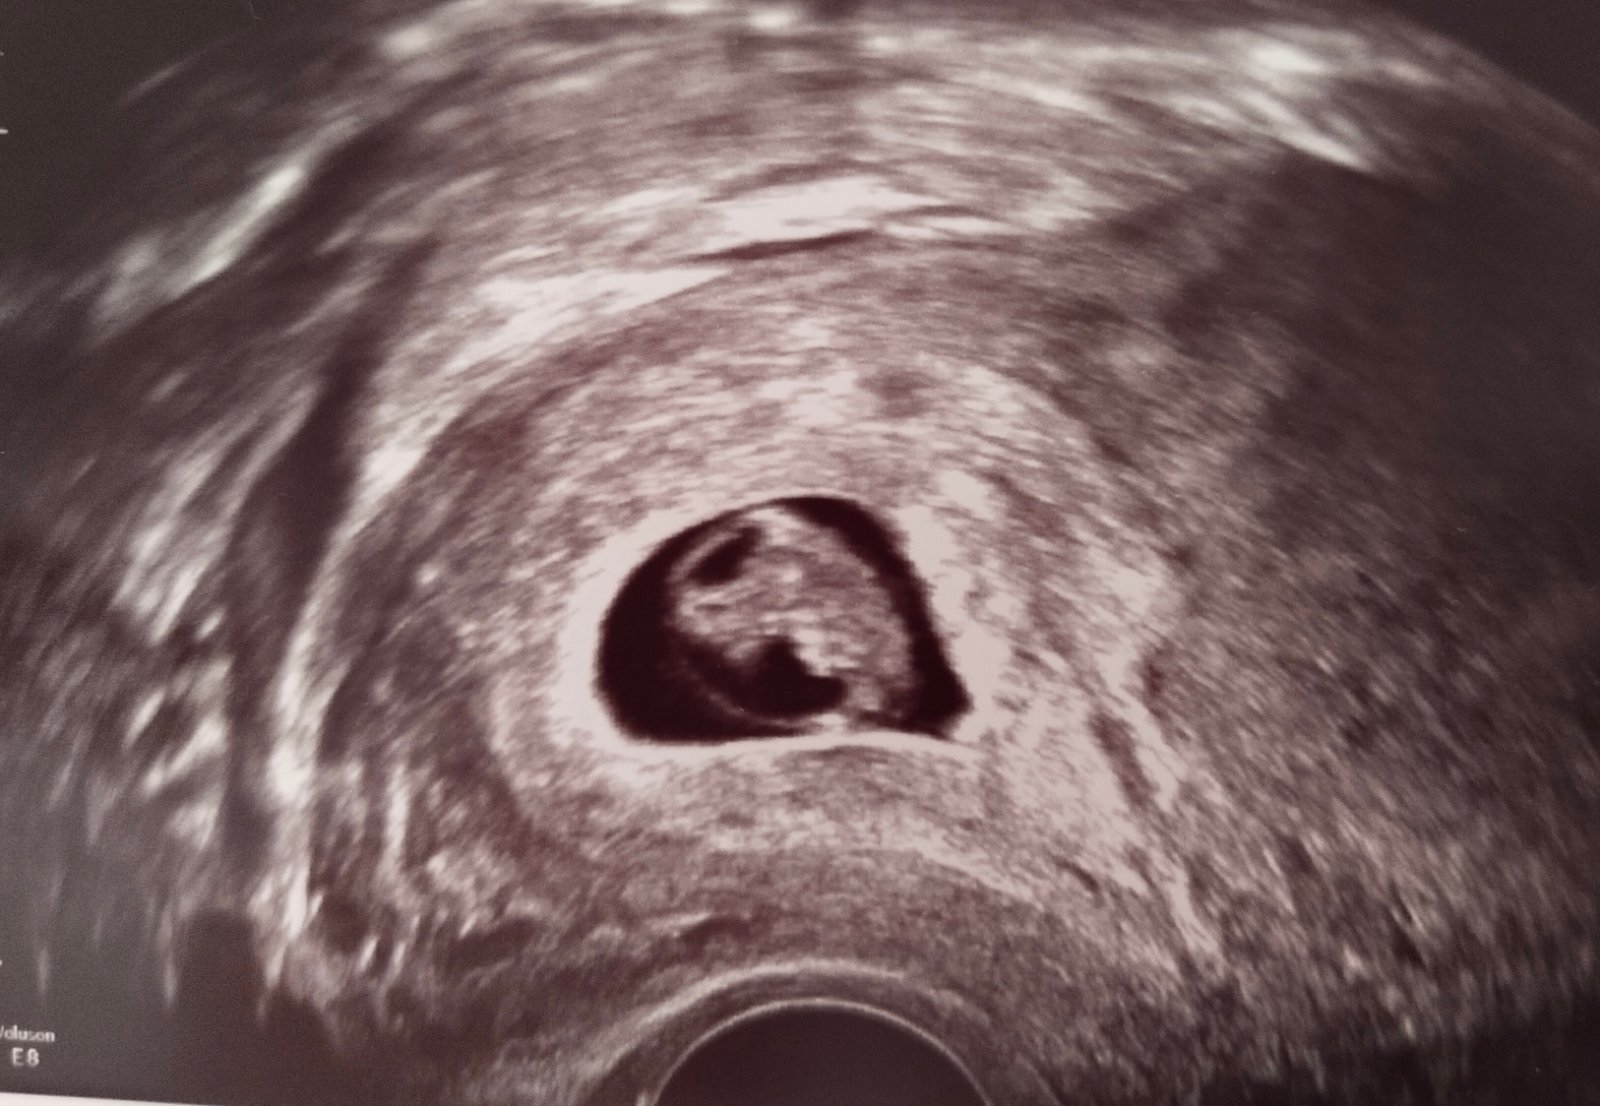

Ahoj.. dneska jsem měla nějaký fofr. 🙈 Tak píši až teď, kdy jsem se konečně zastavila. Ano! U mudr všechno v pořádku. Jsem teď 7+4, srdíčko tluče jak má a plod se zdá být takový, jaký v této fázi být má..🤩❤️ jsem šťastná! I když už jsem to jednou zažila, stejně mě to dojalo..❤️ za 14 dní jdu znovu na kontrolu, kdy mi vystaví tehu kartu a za dalších 14 dní, tedy za měsíc mě čeká první velký screening.

Náš plůdek 🥰